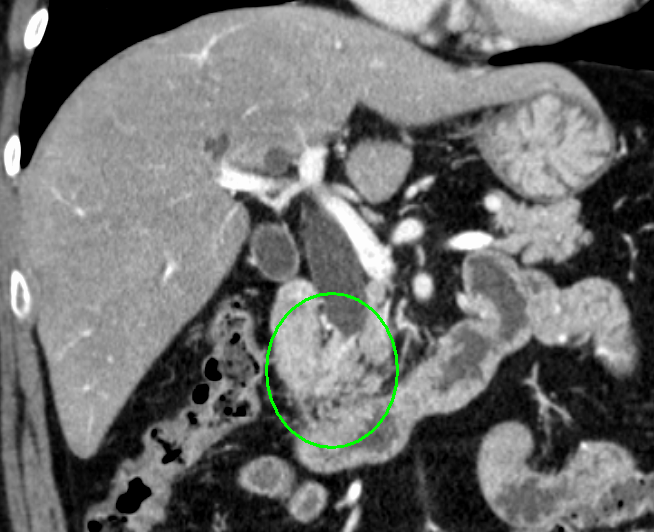

CT画像(遠位胆管がん)